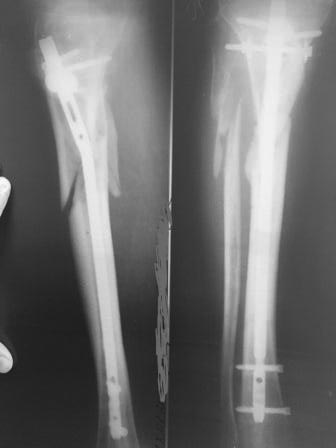

многооскольчатый перелом обеих костей в/з правой голени. Не срастается |

8 месяцев не срастается многооскольчатый перелом в/3 обеих костей правой голени со смещением. Просим Вас помочь. Мужчине 70 лет, ликвидатор Чернобыльской АЭС, резекция 5/6 части желудка. В июне 2019 года получил многооскольчатый перелом обеих костей в/3 правой голени со смещением. В июне поставили аппарат Илизарова. Проходил с ним 4 месяца и безрезультатно. Аппарат сняли и в октябре 2019 года вставили стержень на болтах. К сожалению, в январе 2020 года сделали снимок и срастания нет. стопой шевелит. нога немного сгибается. Просим Вас помочь. Что делать не знаем. Отправляют на инвалидность. Но, хотелось бы поставить папу на ноги. Делать третью операцию? Прилагаю снимок января 2020 года. Есть снимки всех этапов лечения.

Проблема понятна. В принципе, может срастись и в положении как есть. Но лучше бы пересинтезировать хоть тем же стержнем, но с устранением все смещений. Технически это вполне выполнимо, надо только знать и уметь делать все необходимые элементы операции.

Не очень понятно про "немного сгибается". Уж что-что, а условия для восстановления амплитуды движений во всех суставах есть более чем достаточные. По крайней мере, после снятия аппарата ничего даже теоретически не мешает.

Так что надо этим (восстановлением амплитуды движений в коленном и голеностопном суставах) озаботиться в первую очередь. Сращения достичь рано или поздно, так или иначе - все равно получится, а вот ограничение подвижности сустава может стать стойким.